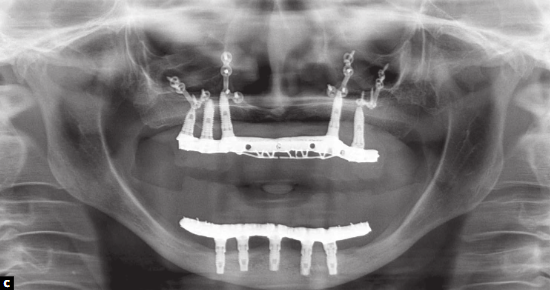

O plano de tratamento compreendeu a realização de três procedimentos cirúrgicos: reconstrução de maxila com enxertia óssea autógena proveniente de crista ilíaca anterior; instalação de implantes em maxila para confecção de prótese total implantossuportada descompensada; avanço maxilar, através de osteotomia do tipo Le Fort I. O planejamento e tratamento foram realizados com sucesso e a paciente relatou estar satisfeita e sem queixas.

Os autores explicam que próteses implantossuportadas, enxertos ósseos e osteotomia do tipo Le Fort I podem ser indicadas para o tratamento de pacientes portadores de atrofia severa que resultem em alterações dentoesqueleticofaciais importantes. De acordo com eles, se faz necessária a elaboração de um planejamento minucioso das etapas, envolvendo os profissionais das especialidades de Cirurgia Bucomaxilofacial e Prótese Odontológica. “A técnica em três etapas cirúrgicas, apesar de conferir ao tratamento uma maior morbidade, parece estabelecer uma maior previsibilidade dos resultados, que pode se traduzir em melhor estabilidade do tratamento”, salientam os pesquisadores.